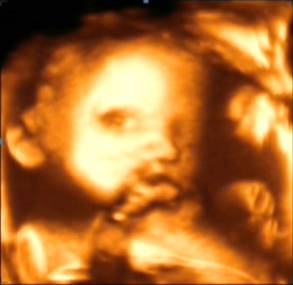

四維彩超就是四維成像技術(shù)(4D),能直觀、立體顯示人體器官的三維結(jié)構(gòu)及動態(tài)、實時地觀察立體結(jié)構(gòu),而以往的二維成像技術(shù)只能顯示人體器官的某一切面。4D技術(shù)的應(yīng)用,為臨床超聲診斷提供了更豐富的影像信息,減少了病灶的漏診,提高了診療質(zhì)量。適用于心臟、肝、膽、脾、胰腺、婦產(chǎn)科、外周血管、表淺器官(如眼球、甲狀腺、乳腺、陰囊等)軟組織各種疾病的檢查。尤其在婦產(chǎn)科方面,對胎兒進行超聲檢查能立體顯示胎兒的顏色、面、各器官的發(fā)育情況,甚至胎兒在母體里的狀態(tài)也可以觀察到;對胎兒畸形,如唇裂、腭裂、骨骼發(fā)育異常、心血管畸形等能早期診斷。

四維彩超還能讓準(zhǔn)爸爸和準(zhǔn)媽媽們了解寶寶在母體里的成長過程,還可以將胎兒不同時期的發(fā)育、活動狀態(tài)儲存。

四維彩超適用于受孕4-6月期間(孕22-28周),主要是輔助二維B超,多方位、全面的觀察胎兒。因孕婦的個體差異,個人的具體時間還請與醫(yī)生聯(lián)系,按醫(yī)囑時間定。因為四維彩超對孕婦和胎兒基本沒影響,所以做檢查時可以通過四維成像技術(shù)觀察可愛的寶寶在子宮里的狀態(tài),享受將為人母的喜悅。